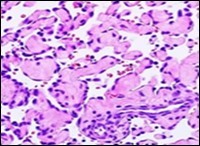

On microscopy, superficial squamous epithelial surface is intact. Sub-epithelial connective tissue stroma exhibits slit-like, vascular spaces. Upon extended magnification, multiple, intravascular papillary projections encompassed within a hyalinised stroma are discerned. Centroidal calcification appears in combination with intravascular, papillary endothelial cell proliferation, lined with singular layer of endothelial cells devoid of cytological atypia6, 7.

Characteristically, the vascular neoplasm denominates numerous papillae within blood vessels. Papillae are coated with singular or dual layer of flattened endothelial cells with an encompassing hyalinised, fibrous tissue core. Vascular lumen is distended with thrombosis. Foci of haemorrhage with fibrinous and purulent exudate are discerned. Tumour perimeter depicts inflammatory granulation tissue. Cholesterol clefts and focal reactive bone formation may concur. Extraneous squamous epithelium may be discontinuous and ulcerated. The neoplasm is devoid of features of malignancy4, 6.

Numerous micro-calcifications can be observed within the lesion which may engender vascular occlusion and tissue necrosis6. Figure 1, Figure 2, Figure 3, Figure 4, Figure 5, Figure 6, Figure 7, Figure 8.

Figure 2 Papillary endothelial hyperplasia delineating papillary articulations with an endothelial cell layer, thrombotic exudate and fibrinous debri (1.